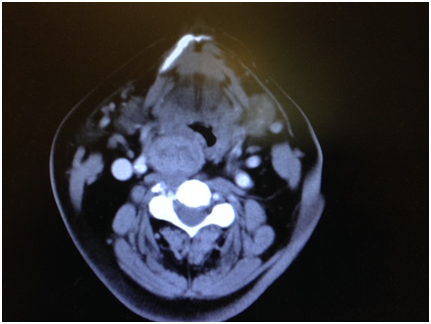

Figure 3 CT scan soft tissue neck showing thyroid enlargement extending up to the level of mandible and base of the tongue on the right side.